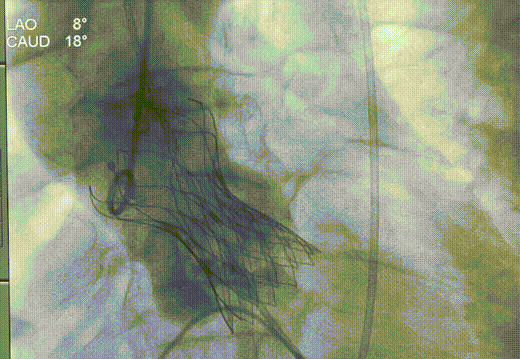

图片

瓣膜释放完成

释放后造影

22球囊后扩

后扩后造影

术后主动脉弓部造影,未发现夹层